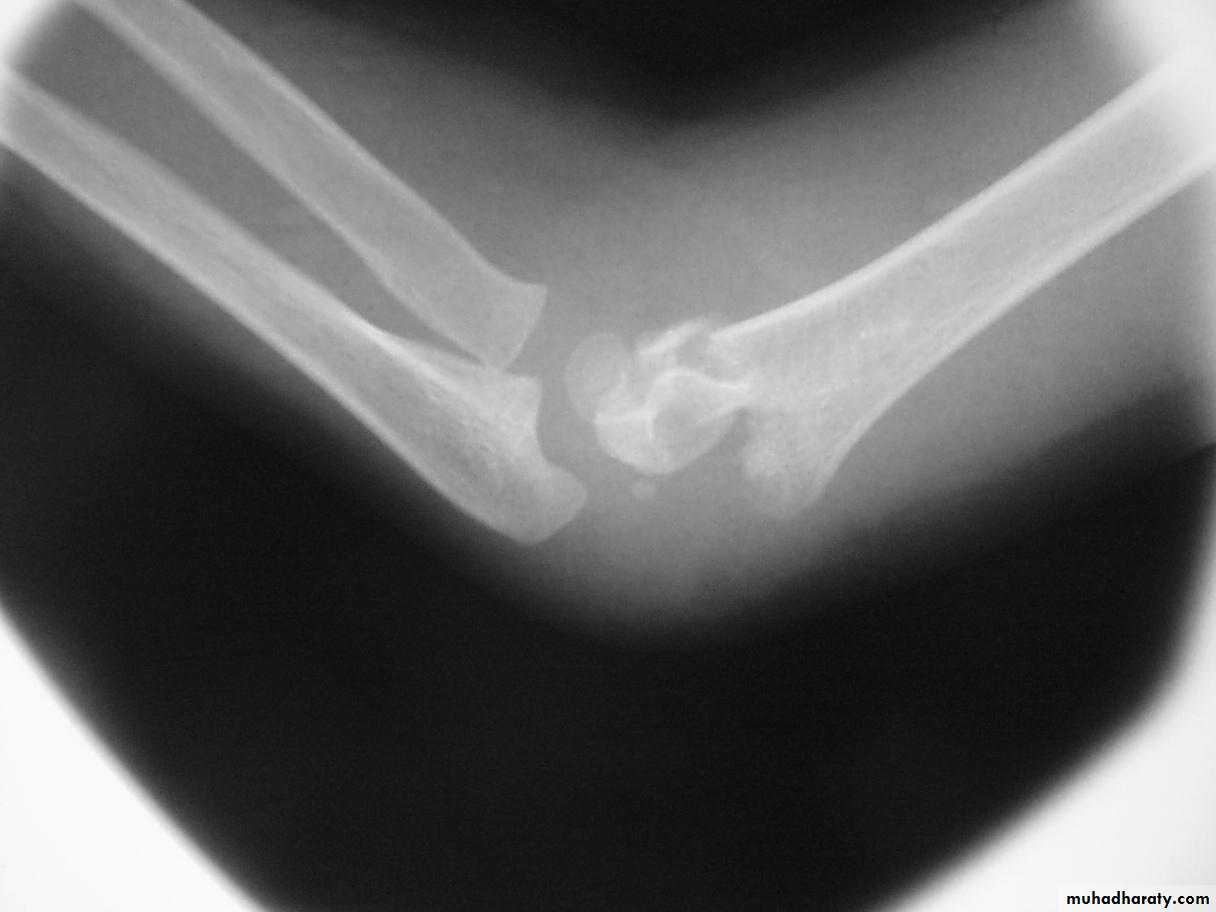

What is the mechanism of injury

for extension type supracondylar fractures ?As the

extended extremityattempts to break

the fall,

the olecranon

is forced

deep into its fossa.

This causes

the humerus to failin the weak metaphyseal

supracondylar area.